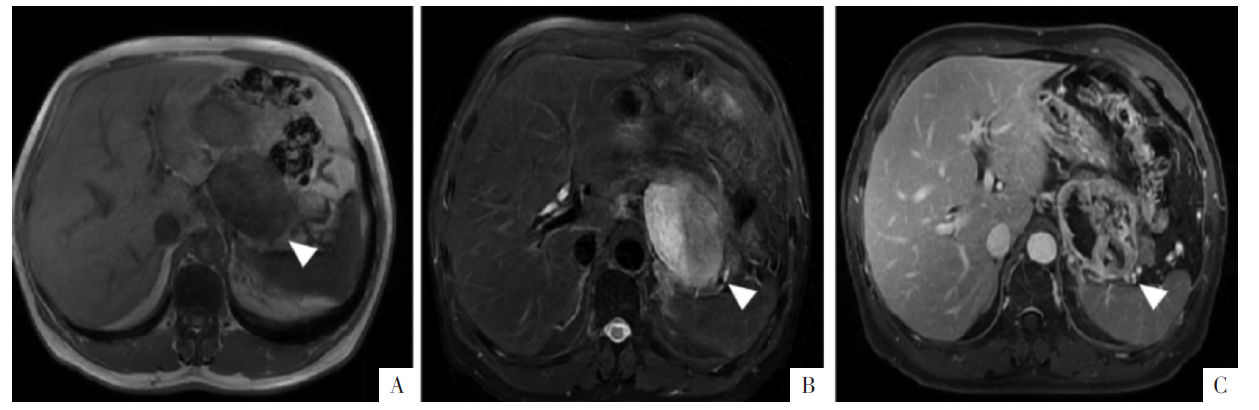

病人男,67岁,腹膜后间隙DDLPS。A-C图分别为横断面T

WI-FS,可见腹膜后团块状影,T

1

WI上呈稍高、低信号,T

2

WI-FS上呈高低混杂信号;增强后实性成分呈不均匀显著强化,可见不强化区。